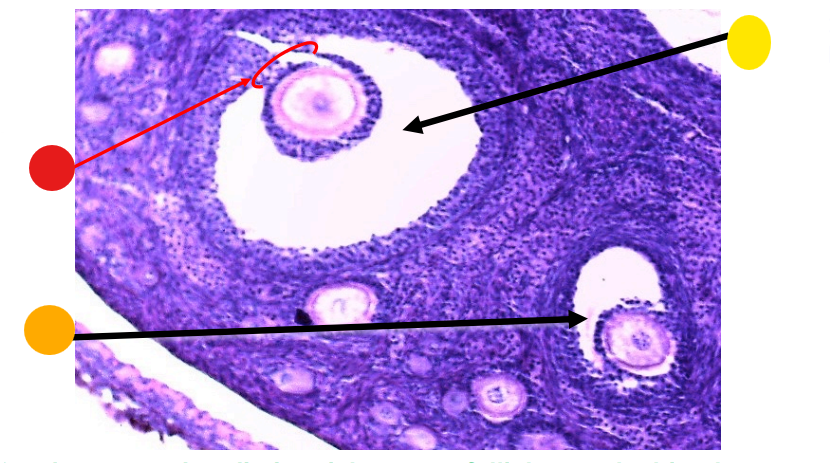

what is this?

ovary

red

primary oocyte

orange

zona pellucida

yellow

granulosa cells

light green

developing thecal cells

What is this

secondary follicle

red

granulosa cells

orange

primary or secondary oocyte

yellow

oocyte nucleus

light green

zona pellucida

dark green

cumulus oophorus

light blue

antrum

dark blue

thecal cells

what is this

tertiary follicle